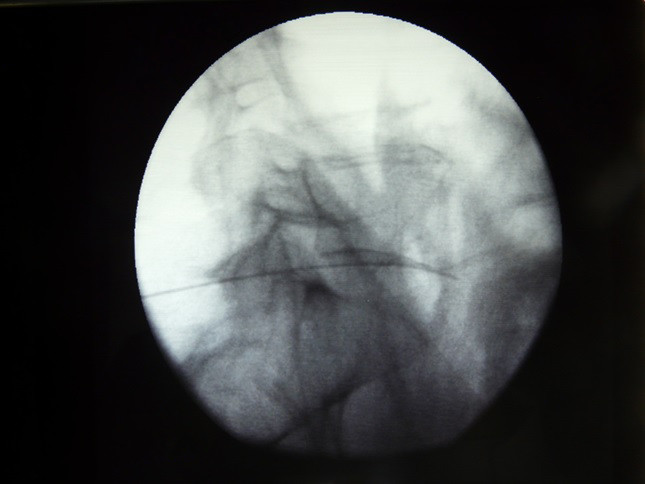

Fig.4. Penetracion de la aguja de Chiba a través del saco tecal y disco intervertebral y su salida en la parte anterior del disco.

5/6